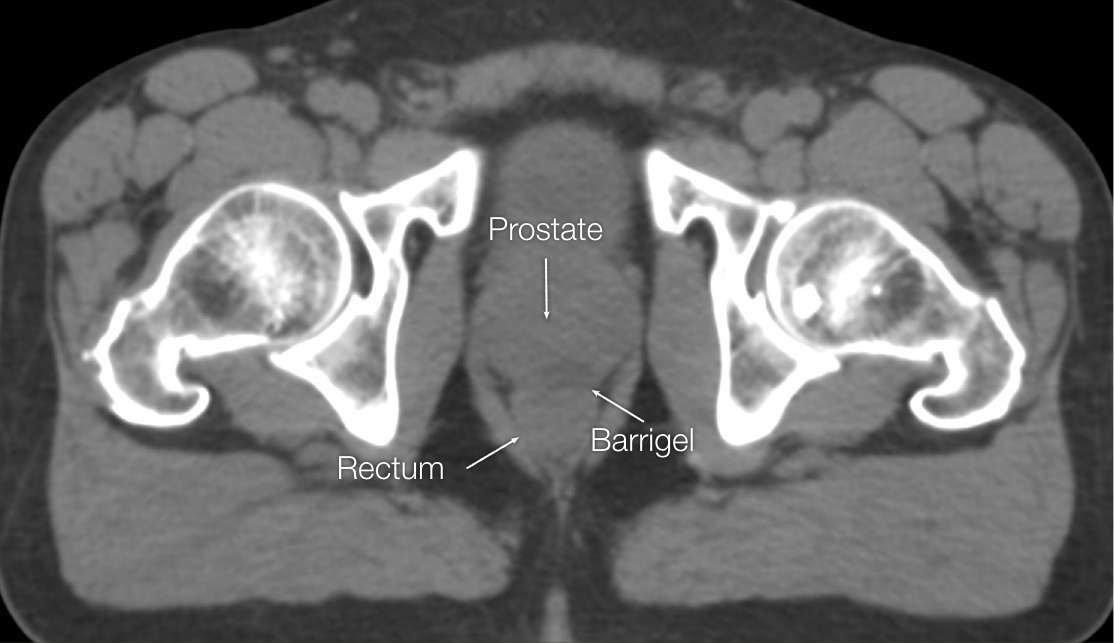

OPTIMIZING CT IMAGES

OPTIMIZING CT

IMAGES

Before (left) and after (right) adjusting window & level settings to enhance contrast and texture

CT images sourced from the Barrigel Pivotal Trial